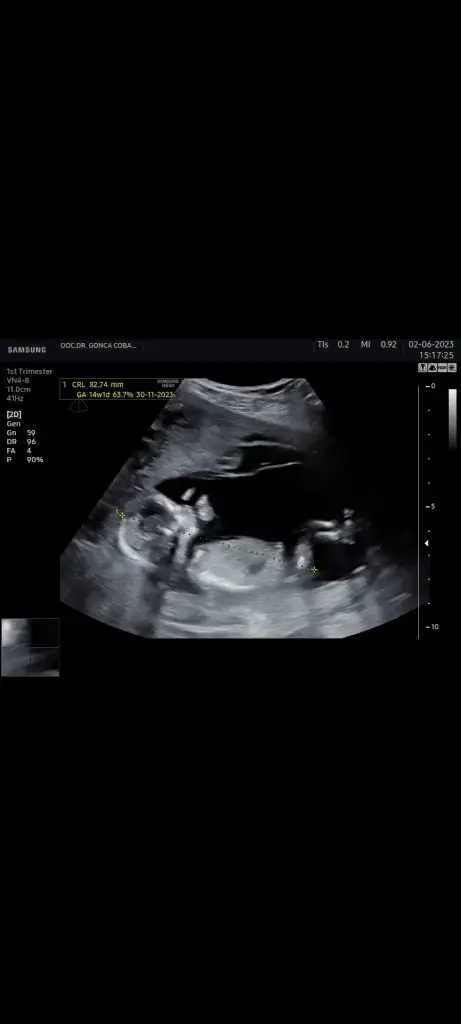

ccinsiyeten anlayan diğer sevgili arkadaşlar rica etsem bakar mısınız? Hepsi karından çekildi. 16 haftalık olduk bugün ama göstermedi cinsiyetini. Bacaklarını kapatmış. 16 haftalık ultrason resmi almayı unuttum. Ayrıntılı ultrasonda nasip olursa artık. Ama anlayan varsa tahminde bulunursa sevinirim.

Eki Görüntüle 3262186 Eki Görüntüle 3262187 Eki Görüntüle 3262188 Eki Görüntüle 3262189 Eki Görüntüle 3262190 ccinsiyeten anlayan diğer sevgili arkadaşlar rica etsem bakar mısınız? Hepsi karından çekildi. 16 haftalık olduk bugün ama göstermedi cinsiyetini. Bacaklarını kapatmış. 16 haftalık ultrason resmi almayı unuttum. Ayrıntılı ultrasonda nasip olursa artık. Ama anlayan varsa tahminde bulunursa sevinirim.